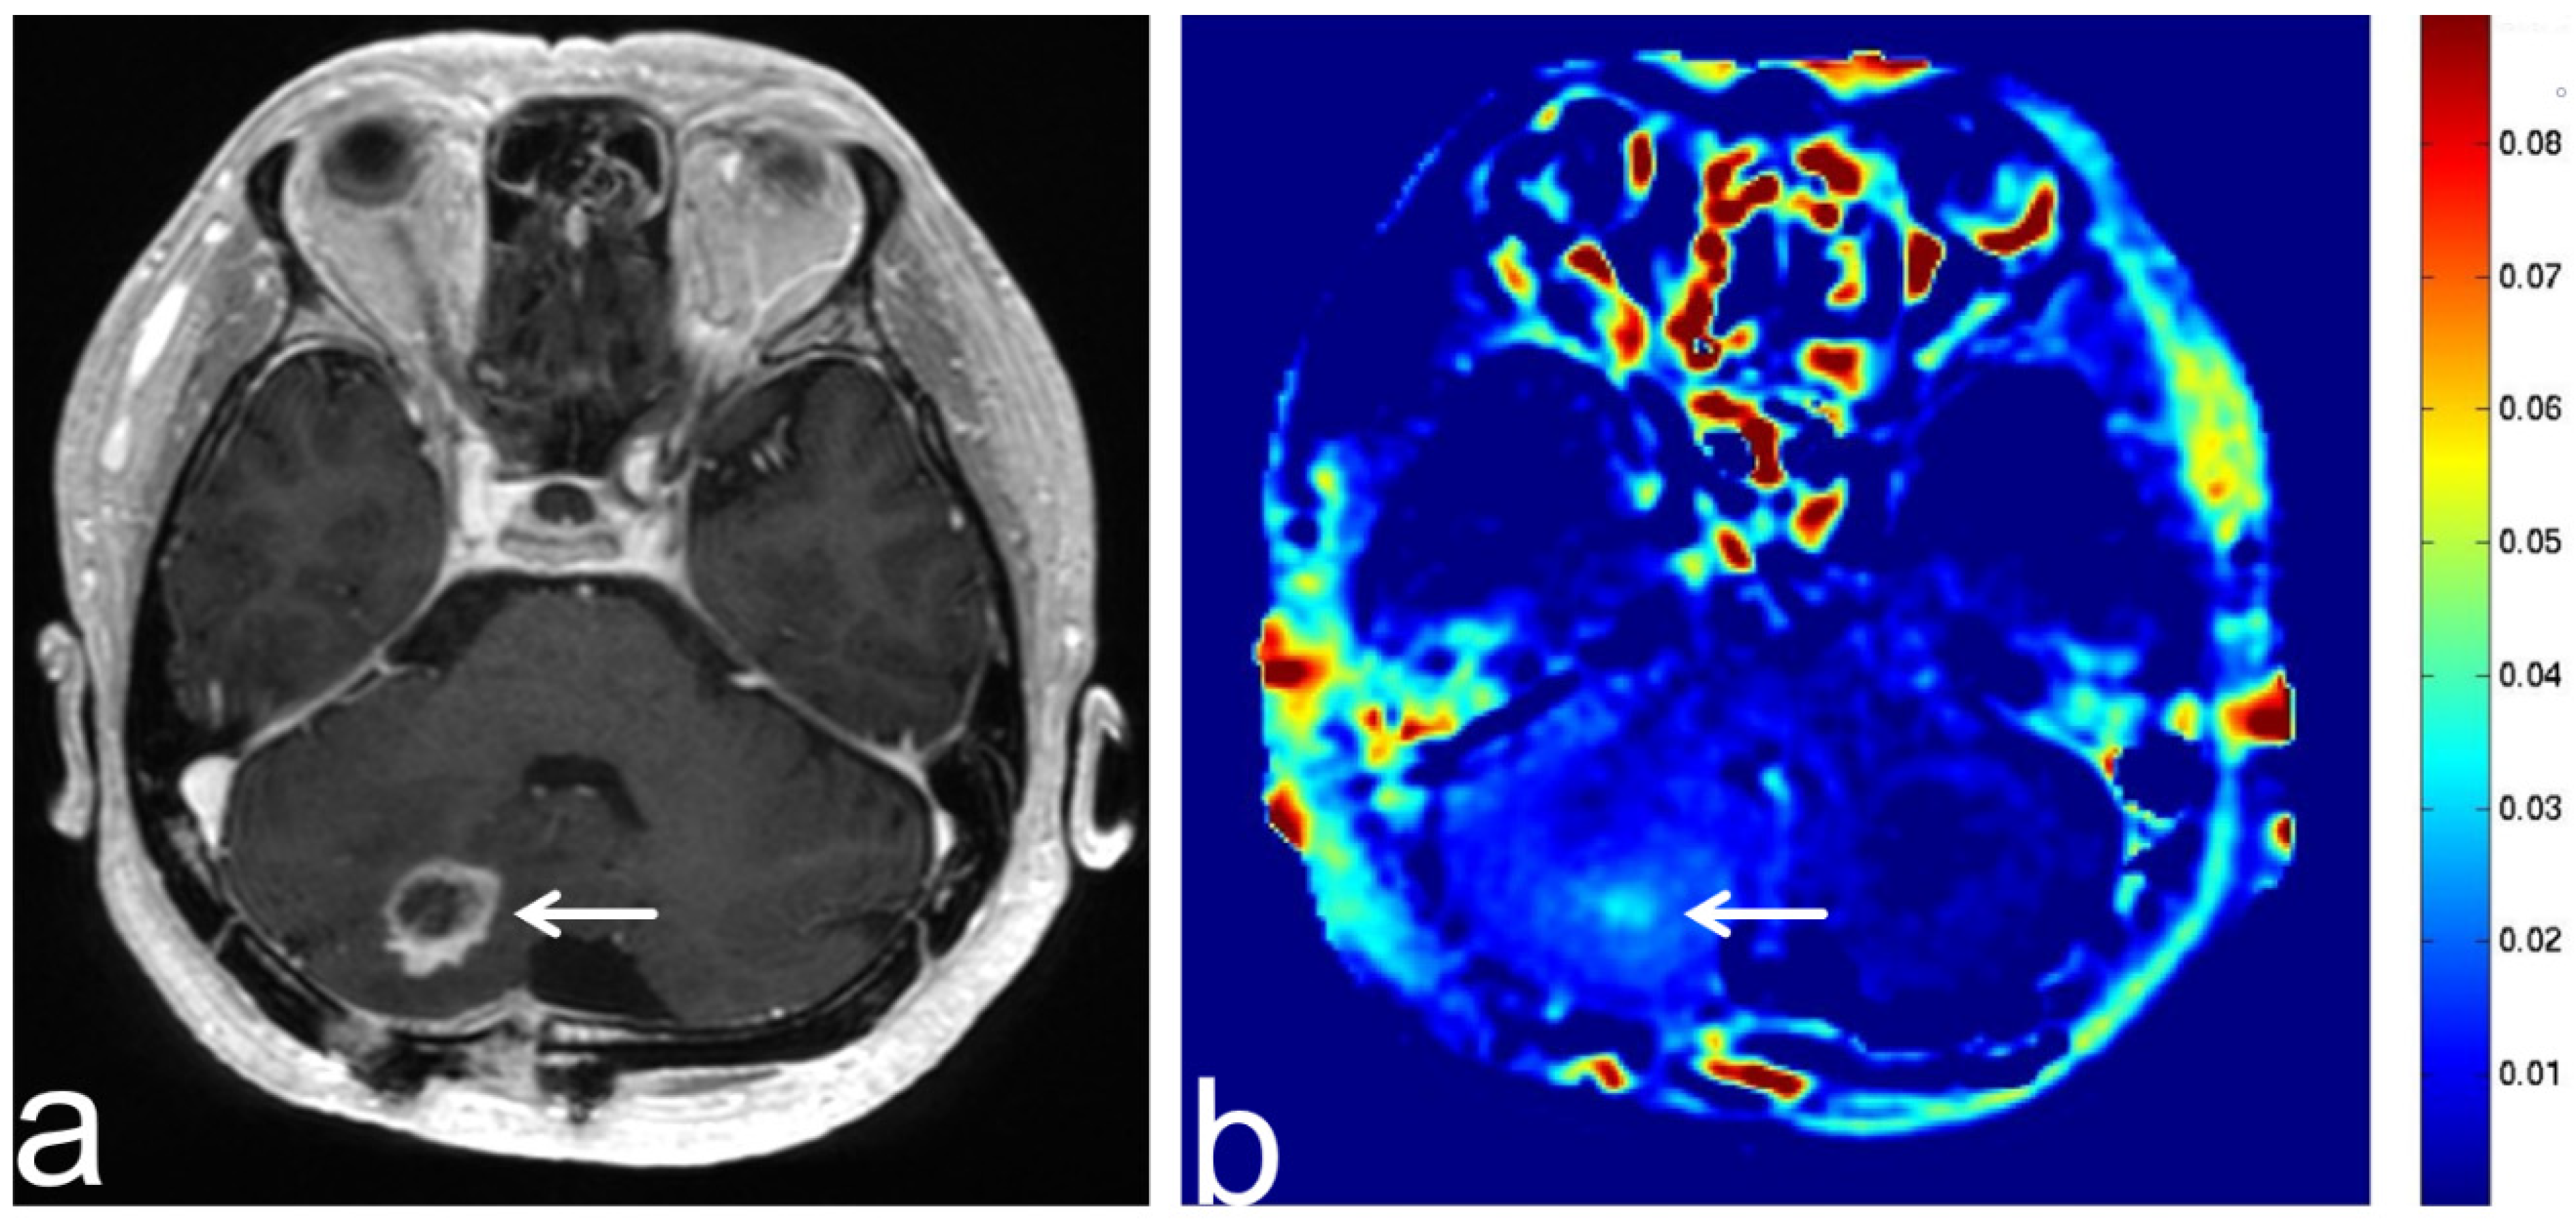

5.5. Brain Metastasis